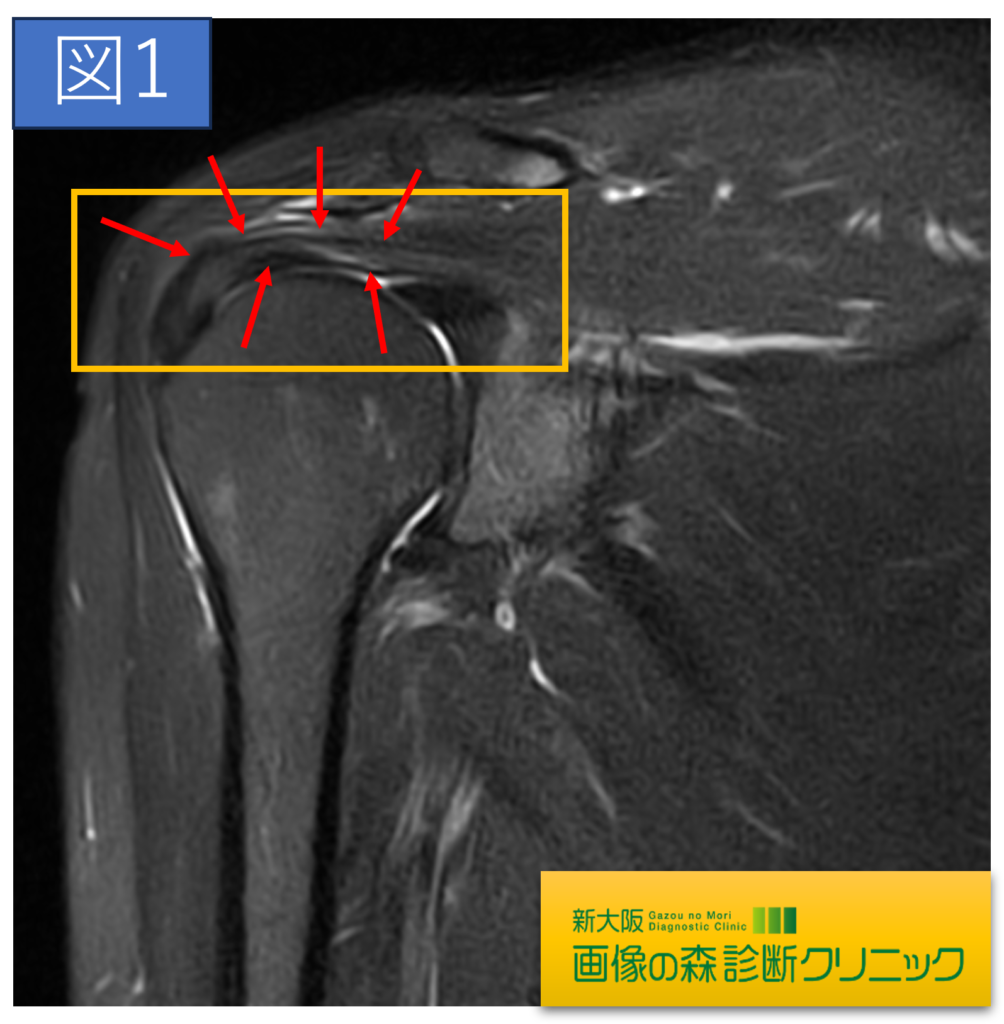

肩関節正常画像(冠状断像)

肩関節症例画像(冠状断像)

症例画像から図1~図4は棘上筋腱の画像です。□内に棘上筋腱の損傷を示します。正常では靱帯や腱は黒く描出されますが、損傷では白く高信号に描出されます。棘上筋腱損傷は、加齢による変性や転倒・スポーツ・仕事などによる外傷が原因となります。

症例画像から図1~図4は棘上筋腱の画像です。□内に棘上筋腱の損傷を示します。正常では靱帯や腱は黒く描出されますが、損傷では白く高信号に描出されます。棘上筋腱損傷は、加齢による変性や転倒・スポーツ・仕事などによる外傷が原因となります。